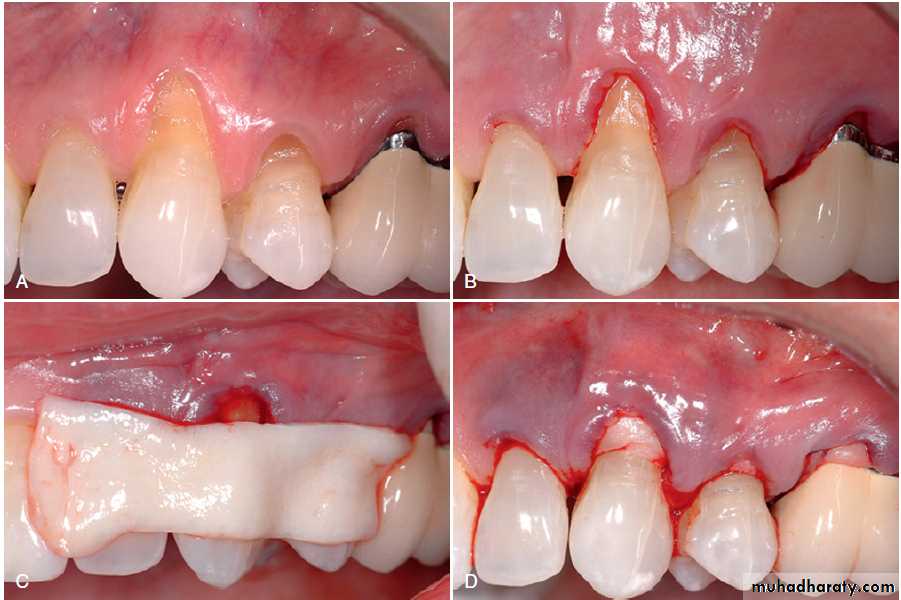

Free Connective Tissue Autografts.(A) Lack of keratinized, attached gingiva buccal to the central incisor. (B) Vertical incisions to prepare the recipient site. (C) Recipient site is prepared. (D) Palate from which connective tissue is removed for donor tissue. (E) Removal of connective tissue. (F) Donor site is sutured.

Gingival Augmentation Apical to Recession

Free Connective Tissue Autografts.

(G) Connective tissue for the graft. (H) Free connective tissue is placed at the donor site. (I) Postoperative healing at 10 days. (J) Final healing at 3 months. Notice the wide, keratinized, attached gingiva.